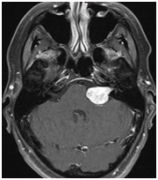

听神经瘤,也被称为 前庭神经鞘瘤 ,是一种良性的,一般生长缓...

听神经瘤 是耳蜗或前庭神经增厚的情况。它可能导致听力丧失和...